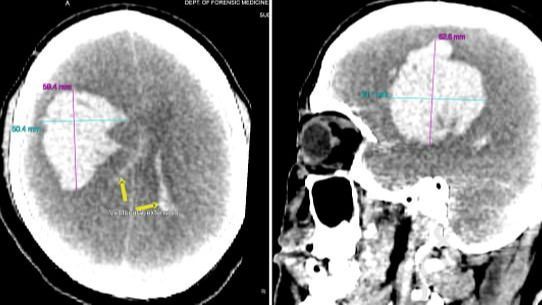

La autopsia mostró que la causa había sido una hemorragia cardiovascular. El Dr. Jay Narayan Pandit, del Departamento de Medicina Forense del Instituto de Ciencias Médicas de toda la India, dijo que las exploraciones post-mortem revelaron una masa de 300 g de sangre coagulada. Los autores dijeron que publicaron el caso para crear conciencia sobre los riesgos de tomar el medicamento para la disfunción eréctil sin consejo médico.